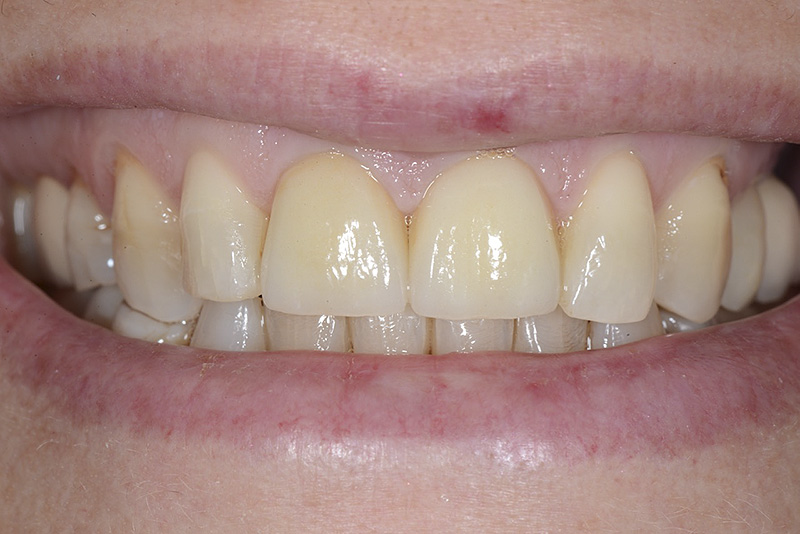

PREMESSA: in seguito all’estrazione dell’incisivo laterale superiore di destra, resasi necessaria per cause batteriche, si decide di affrontare il caso con il posizionamento di un impianto in sostituzione dell’elemento mancante dopo guarigione del sito infetto. Con tecniche rigenerative sia dei tessuti ossei mancanti a causa dell’infezione pregressa, sia dei tessuti gengivali che appaiono inizialmente troppo spostati in alto, si ripristina una corretta morfologia delle parabole (contorni) gengivali e delle papille interdentali (triangoli di gengiva tra due denti vicini).

Vengono utilizzati 2 tipi di provvisori: il primo, cementato ai denti vicini, viene utilizzato dal momento dell’estrazione del dente fino ad impianto osteointegrato (circa 6 mesi); il secondo, avvitato direttamente all’impianto, ha una funzione di prova estetica ma soprattutto di guida per la maturazione dei tessuti gengivali peri-implantari portandoli verso la maturazione completa prima di posizionare la corona finale in disilicato di litio.